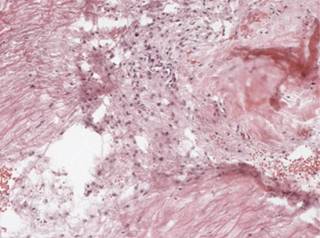

Figure 1: Immersed in the yellow ligament there is accentuation of the vascular pattern with. In this case with hyalinization of the vascular walls.